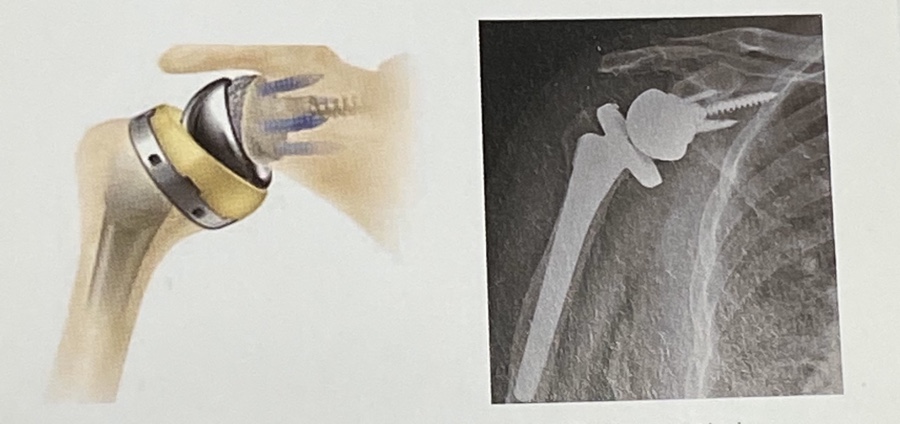

3.역행성 인공관절 치환술

회전근 개 관절병증, 골유합이 힘든 고령의 근위

상완골 복잡골절.인공관절 재치환술시 시행합니다.

일반적 관절 치환술과는 달리 관절와 부분이 볼, 그리고

상완골 부분이 소켓 형태로 된 인공관절로서

회전근개가 없는 등의 특수한 경우에 사용 됩니다